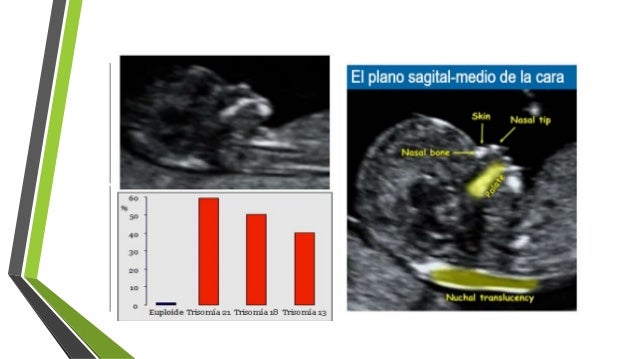

• Un análisis de sangre y una prueba de ultrasonido durante el primer trimestre del embarazo.El ultrasonido puede detectar fluido en la nuca del feto, lo que a veces indica la presencia del síndrome de Down

Resultado de imagen para tamizaje sindrome down